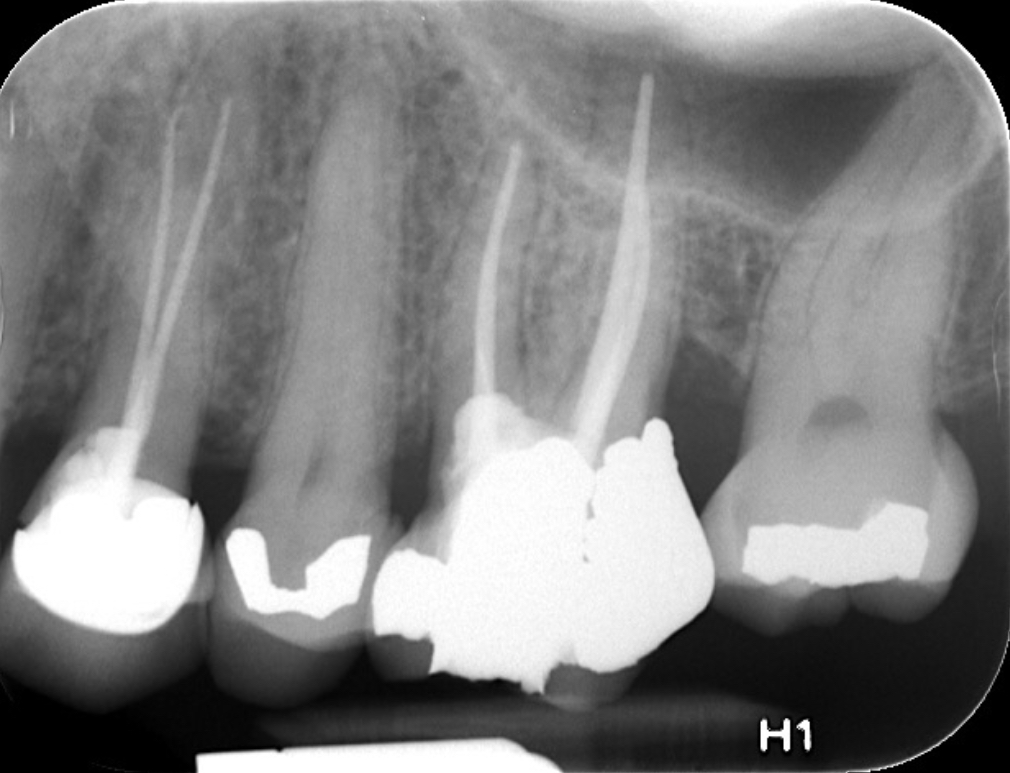

Fig 4. Preoperative radiograph showing aggressive external root resorption and thin dentinal walls.

Figure 4

Clinical procedure: Regeneration of the endodontic pulp space is indicated for cases with very thin dentinal walls and an open apex that is more than 1 mm in diameter radiographically (Figure 4). Disinfection of the root canal system is performed using sodium hypochlorite irrigation followed by a triple antibiotic paste dressing that is left in place for 1 week. At the second visit, ethylenediaminetetraacetic acid (EDTA) is used to condition the dentin walls, which results in the release of growth factors, and bleeding is stimulated in the periapical tissues (where stem cells are located), with the aim of filling the pulp space with a stable blood clot, which would serve as the scaffold. MTA is then placed at the canal orifice in contact with the clot to protect it from coronal microleakage (Figure 5 and Figure 6). In time, the clot should be replaced with a reparative tissue of variable composition, and the root walls should continue to thicken due to the deposition of a dentin-like material on the pre-existing root dentin27,28 (Figure 7 and Figure 8).